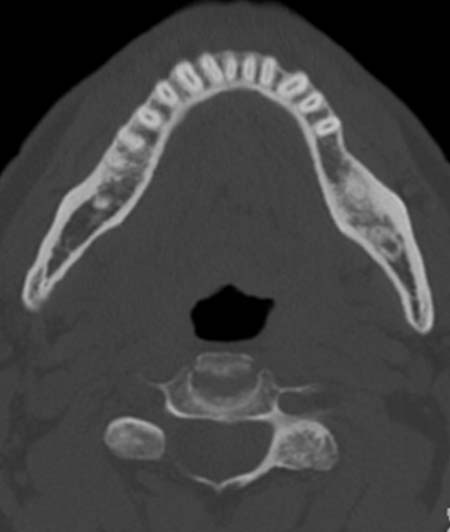

Im

Knochenfenster des CT des Unterkiefers kommt links eine umschriebene

milchglasartige Verdichtung zur Darstellung.